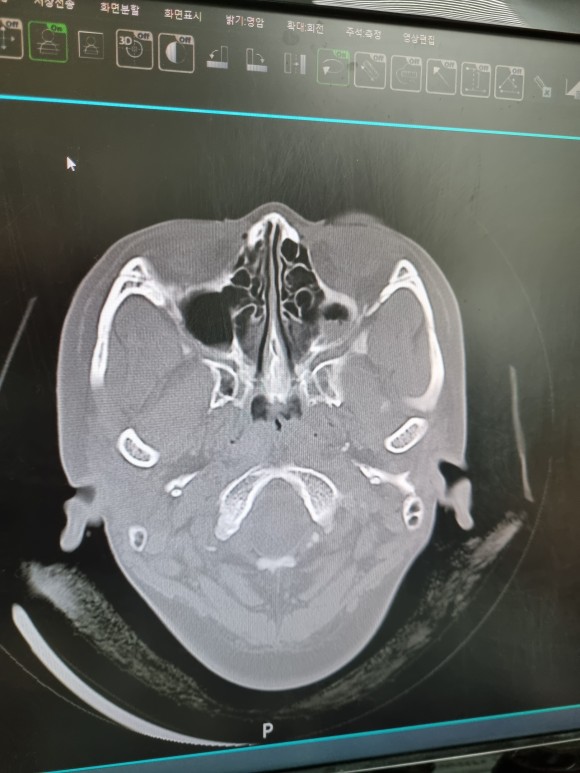

뇌의 시티를 찍으면서

부비동도 함께 볼 수 있다.

부비강염 치료

사진상으로는 아직 절반도 빠지지 않은 염증ㅠㅠ

부비강염

왼쪽에도 약간의 염증이 있지만 정상수준

오른쪽에는 반 이상 하얀 무언가가 가득 찬 그림이 보이시죠?

(새까맣게 비어있는 것이 정상입니다)